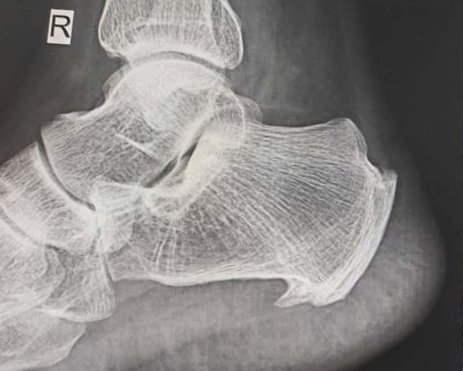

跟骨骨刺的微創(chuàng)治療

跟骨骨刺也叫跟骨骨質(zhì)增生。好發(fā)于肥胖、運動多的人。肥胖的人由于體重大,足跟受力多,所以容易骨刺。而運動多的、如跑步、爬山、打球,足跟反復(fù)受足底筋膜和肌肉的牽拉,也容易產(chǎn)生骨刺。骨刺會刺激足底筋膜,產(chǎn)生筋膜炎,會走路疼痛。所以,需要治療。減少活動或運動。口服抗炎鎮(zhèn)痛藥,有止痛消炎作用。也可以膏藥敷帖。如果以上效果不好或疼痛反復(fù)發(fā)作,影響走路,進行關(guān)節(jié)鏡下微創(chuàng)治療。在關(guān)節(jié)鏡下去除骨刺,手術(shù)半小時左右。6小時后可以走路。由于去除了骨刺,并對筋膜進行了松解,不光是解除疼痛,復(fù)發(fā)的概率也很低。切口小,微創(chuàng),住院兩天,臨床取得了很好的療效。